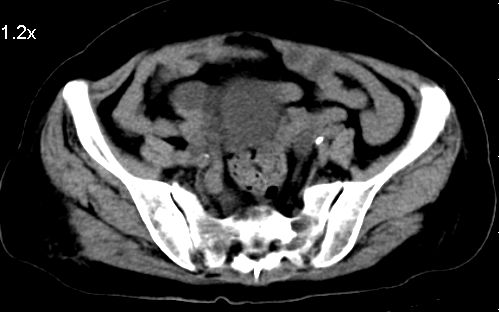

标题: CT10133:F、74岁,反复血尿10天。 [打印本页]

标题: CT10133:F、74岁,反复血尿10天。

膀胱充盈可,壁光滑厚薄尚均匀,其内下方可见不规则的致密影,建议做膀胱镜检查

考虑膀胱癌可能性大伴双侧输尿管下端扩张.

膀胱后壁见不规则致密影,我们遇到这样的病人都再做一次俯卧位扫描;排出膀胱内凝血块。

1.膀胱后壁见不规则致密影,占位?膀胱内凝血块?建议俯卧位扫描、膀胱镜检查.

2.双侧输尿管下段扩张.

膀胱三角区不规整软组织改变,双侧输尿管扩张,所以占位性病变肯定首先考虑,建议改变体位扫描除外游离血块影,但老年人出血原因一定要查明。